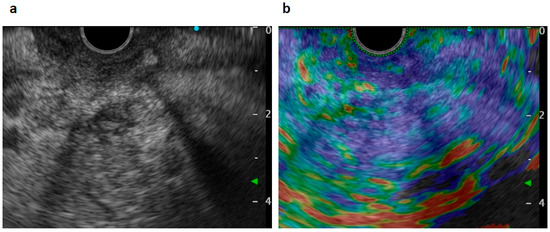

Figure 3.

Endoscopic ultrasonography (EUS) views. A heterogeneous low-echoic mass was seen by scanning from the duodenal bulbs (a). Elastography showed a heterogeneously hard mass lesion at the pancreas head (b).

An 82-year-old Japanese female was referred to our hospital after a month of complaints of upper abdominal discomfort. First, she visited the nearest hospital and underwent upper gastrointestinal endoscopy that pointed multiple erosions and an extrinsic compression at the posterior pylorus. Medication had been initiated using nizatidine, rebamipide and oxetacaine, but it was not effective. She had a history of hypertension, but her family history was unremarkable. Blood tests showed modestly elevated IgG (1950 mg/dL, normal range: 870–1700 mg/dL) and C-reactive protein (0.43 mg/dL, normal range: ≤ 0.3 mg/dL) but normal readings for other factors, including serum tumor markers (carcinoembryonic antigen, carbohydrate antigen, and soluble IL-2 receptor), HbA1c, and IgG4 (66.1 mg/dL, normal: 4.5–117 mg/dL). Enhanced computed tomography (CT) demonstrated an ill-enhanced mass, 5 cm in size but with unclear margins, located at the pancreas head (Figure 1a,b). Upper gastrointestinal endoscopy revealed a submucosal tumor (SMT) with an apical erosion approximately 1.5 cm in size at the duodenal bulbs (Figure 2). Several faintly enlarged lymph nodes were seen around the pancreas head, but no nodules suggestive of metastasis were visible in the liver or the lungs. Endoscopic ultrasonography (EUS) demonstrated a heterogeneous, low-echoic mass at the pancreas head and body, but no adhesion to the common bile duct. EUS elastography revealed a hardness of the pancreas lesion (Figure 3). Forceps biopsy (Radial Jaw™4, Boston Scientific Japan, 2.2 mm, Tokyo, Japan) from the duodenal SMT was not informative, but EUS-guided fine needle aspiration biopsy (FNAB) showed abundant spindle myofibroblast tissues with eosinophilic and lymphoplasmacytic cell infiltration (Figure 4). FNAB was performed with two punctures from the duodenal bulbs, with each puncture performed with 10 strokes using a 22-gauge Franseen-tip needle (Acquire™, Boston Scientific Japan) with 10 mL of negative pressure. No malignant cells were seen. The spindle cells were positive for anti-smooth muscle antibody (ASMA) and desmin but negative for discovered on GIST-1 (DOG-1), c-Kit, CD34, S-100, and ALK. Only six IgG4-positive cells were recognized in high-powered views, and no obliterative phlebitis or storiform fibrosis was detected. These findings led to the diagnosis of IMT.